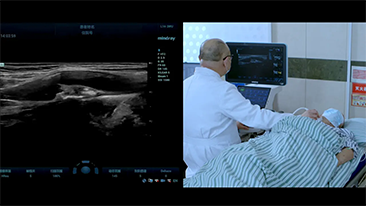

Covid-19 ŌĆō Testtijd voor mensen en apparaten

Als gevolg van het coronavirus hebben ziekenhuizen en medisch personeel nieuwe werkmethoden ontwikkeld, waaronder, in acute omstandigheden, afstand houden, strikt gebruik van persoonlijke beschermingsmiddelen (PBM's), handen wassen en dagelijkse desinfectie van apparatuur. Draagbare, zeer mobiele en veelzijdige apparatuur ging een belangrijke rol spelen bij point-of-care (POC), met name wanneer afdelingen en operatiekamers over verschillende verdiepingen verspreid liggen en de toegang tot gespecialiseerde apparatuur van het allergrootste belang is.